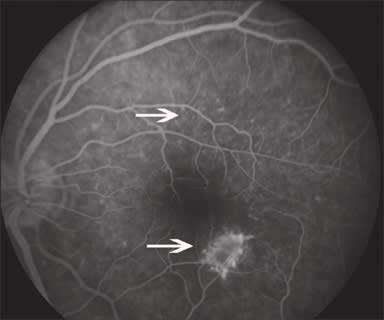

On initial exam, his vision was 20/25 in both eyes, anterior segment was benign and there was no evidence of vitreal cell. Inferiotemporal to the fovea of his left eye, he had a hypopigmented lesion deep to the retinal vessels (Figures 1A and 1B). On fluorescein angiography (FA), the hypofluorescent lesion appeared to be a cluster of hyperfluorescent dots (Figure 2), which were more apparent than on clinical examination. These dots appeared to stain slightly during late-phase angiography (Figure 3). Early-phase indocyanine green angiography (ICG) was unremarkable; however, during late-phase angiography, there were small hypofluorescent dots overlying larger hypofluorescent spots (Figure 4). There was also a lacy, irregular ring of hypofluorescence at the margin of the optic disc. The hypofluorescent spots appeared more numerous than was apparent on either fluorescein or on clinical exam. Microperimetry was performed. The imaged blind spots on microperimetry (Figure 5) corresponded to the hypopigmented areas noted on ICG. One week after the initial visit, multiple hyperfluorescent white dots appeared on the FA (Figure 6); during this visit, the patient had vitritis that resolved spontaneously within a few days. Repeat microperimetry (Figure 7A) and ICG (Figure 7B) showed improvement 6 weeks after the initial visit and after a course of steroids. Imaging supports a diagnosis of multiple evanescent white dot syndrome (MEWDS). RP

Figure 2. Laminar phase angiography showing the lesion as a cluster of white dots (arrow).

Figure 3. Late-phase angiography showing staining of the white dots (arrow).